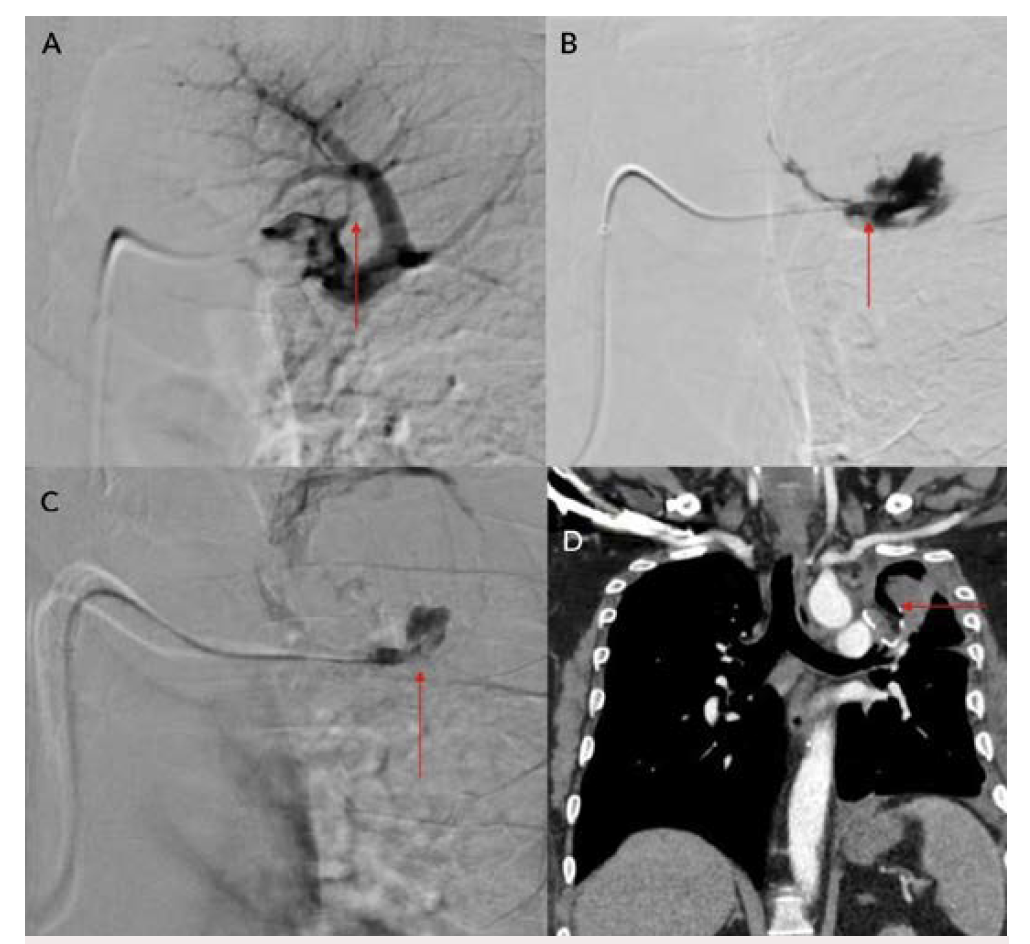

Eight patients were included during this study period; all were men between ages 34 and 61 (Table 1). Positivity to COVID-19 RTPCR test was detected over a period of 2 to 6 months prior to the acute hemorrhage. Six patients presented with massive hemoptysis; 2 presented with severe epistaxis. A contrast-enhanced computed tomography angiography was done in all patients. All 6 patients who presented with massive hemoptysis were detected to have pulmonary arterial pseudoaneurysms with associated cavitary lesions in the lungs (Figure 2). Among the 2 patients who presented with nasal bleed, 1 had a biopsy and culture-proven invasive fungal sinusitis with an internal maxillary artery pseudoaneurysm, probably of mycotic etiology. The second patient also diagnosed with invasive fungal sinusitis had multiple sinonasal debridements outside before presenting with massive epistaxis wherein a diagnosis of internal carotid artery pseudoaneurysm was made, probably secondary to iatrogenic or mycotic etiology. The presence of concomitant COVID-19 infection in these patients predisposed them to impairment of cell-mediated immunity, immune dysregulation, and a decrease in CD4 and CD8 counts, increasing their vulnerability to fungal infections. In 6 patients it was possible to obtain samples for fungal elements through biopsy. Endovascular embolization was performed under local anesthesia in 7 patients, and under general anesthesia in 1 patient. Different embolic agents were used: coils (Figures 3A and 3B), Amplatzer vascular plug (Abbott) (Figures 4A and 4B, Figures 5A and 5B), and glue (Figures 6A and 6B). However, 2 patients underwent lobectomy for extensive parenchymal disease apart from pseudoaneurysm. One patient with pulmonary artery pseudoaneurysm had contrast extravasation into the cavity during the procedure. All patients had cessation of hemorrhage. However, 2 patients required pulmonary lobectomy because of extensive parenchymal disease after embolization for the pseudoaneurysm.

COVID-19 infection has affected people worldwide since 2020 after its initial outbreak in Wuhan, China. It has caused significant mortality and morbidity, causing millions of deaths to date. COVID-19 infection is known to affect multiple organs such as the lungs, heart, brain, and skin, with the lung being most common.1 Patients with COVID-19 usually present with complaints of fever, cough, malaise, and difficulty breathing.1 Diabetes mellitus is an independent risk factor for COVID-19 infection.1 Fungal infection was a known complication following COVID-19 infection, especially in those with poorly controlled blood sugar and who have been treated with immunosuppressive agents such as steroids.2,3 Pulmonary complications following COVID-19 infection were mainly related to fibro-cavitary changes.3-5 Hemorrhage following fungal infection was mainly due to vascular involvement and formation of pseudoaneurysm.6 Patients with severe COVID-19 infection may have endothelial inflammation and secondary fungal infection, leading to pseudoaneurysm formation with a risk of increased bleeding.5,6 Fungal sinusitis following COVID-19 infection is a well-known entity that can cause bleeding due to the involvement of the internal and external carotid vessels.2,3,5 Extracranial carotid artery aneurysms are found most frequently in the common carotid artery at or near the bifurcation, less frequently in the internal carotid artery (Figures 7A and 7B), and least often in the external carotid artery.7,8 Ongoing studies of the precise molecular underpinnings of mycotic pseudoaneurysms suggest that arterial wall breakdown is likely caused by matrix-degrading enzymes produced by either seeded bacteria or inflammatory cells of the host response.6 Diabetes and fungal infections are more frequently documented, which could result in mycotic aneurysm, spontaneous rupture, and massive hemorrhage.2,3,5

Pulmonary artery pseudoaneurysm is a rare but important entity because of its high risk of life-threatening hemorrhage.2,5,9,10 Peripheral branches of the lower lobe pulmonary artery are most commonly affected.2,5,10 A pseudoaneurysm is different from a true aneurysm because there is no wall except for the hematoma that is surrounding and containing it.6,9,11,12 The etiology of a pulmonary artery pseudoaneurysm is inflammatory erosion secondary to tuberculosis (Rasmussen aneurysm), necrotizing pneumonia, bacterial endocarditis, mucormycosis, or vasculitides (Marfan syndrome, Behçet’s disease, etc.). Other causes include necrotic cavitary lung carcinoma, congenital heart disease, and traumatic injury. Iatrogenic pseudoaneurysm secondary to pulmonary artery catheter placement has also been reported.4-6,9-11 Internal maxillary artery pseudoaneurysm is rare and is more commonly encountered following trauma and iatrogenic injury (Figures 8A and 8B).7,8,13 These patients present with massive or moderate bleeds, which can lead to death in about 50% of cases if left untreated.2,4 The most common artery leading to hemoptysis is the bronchial artery, which constitutes around 80% to 90%.4,5,13 Hemoptysis related to the pulmonary artery constitutes around 10%.10,14 Multidetector computed tomography (MDCT) pulmonary angiography is the modality of choice to diagnose pulmonary artery aneurysms.2,9,10,12 It provides detailed information about the presence, number, size, shape, and origin of pulmonary artery aneurysms.2,9,10 MDCT also allows detailed assessment of the orientation and size of the aneurysmal sac and size of the neck on multiplanar reconstruction.2,10 It also gives an overall idea about the pathology, and the involved lung segment eventually helps in planning the treatment accordingly.4,10,12,14 Digital subtraction angiography has the advantage of allowing endovascular intervention at the time of diagnosis.4,12,14 Ultrasound and magnetic resonance imaging are also used in cases of aneurysms involving neck vasculature.2,14,12